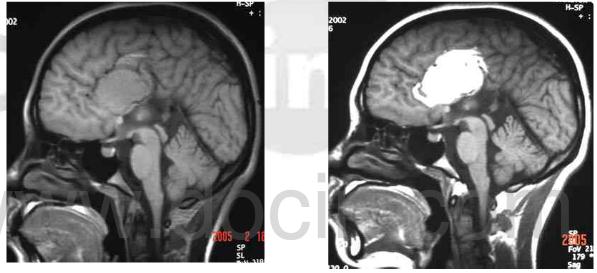

来到我们医院之后,我们给他做了一个脑部的磁共振检查

结果,我们在他脑部发现了异常的信号,经过分析,是脑部的脂肪瘤

颅内的脂肪瘤,白色的亮点处就是脂肪瘤

正是这个重大的脂肪瘤压迫和刺激了周围的大脑,使大脑产生异常放电,引起他发生癫痫,出现四肢抽搐、口吐白沫、神智丧失的症状。

由于这个脂肪瘤持续存在,所以吃抗癫痫药物效果很不好。

最后,我们对他进行了手术,将脑内的脂肪瘤切除后,他的癫痫症状也得到了控制。